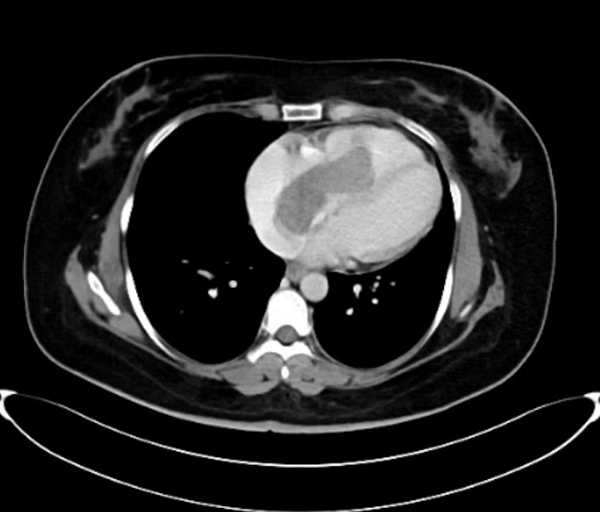

今年39岁的王女士觉得自己活动后稍有憋喘,开始还以为是变胖了,也就没在意,后来活动后憋喘的症状逐渐加重,这才到当地医院就诊。当地医院心脏彩超提示患者右心房占位,考虑黏液瘤,王女士慕名来到省立医院东院心外科。术前心脏彩超检查提示右房占位与下腔静脉关系不清,主管医师张杰敏锐的察觉到患者的肿瘤可能没有预想的那么简单,于是立即为王女士安排了妇科B超、下腔静脉CTV、肺动脉CTA检查,最终的检查结果验证了张杰医师的判断,王女士心脏里的占位不是一般的粘液瘤,影像学上更考虑血管平滑肌瘤。这是具有恶性生长行为的良性肿瘤,沿左侧子宫静脉,左侧卵巢静脉,左肾静脉近心段走行,如同藤蔓一样由下腔静脉进入右心房,随心跳而往返于右房右室之间。

手术当天,在麻醉手术科团队的保驾护航下,妇产科副主任医师李娜首先成功完整切除患者全子宫双附件,去除了因激素引起肿瘤复发的隐患。随后,普外科主任医师张小桥和血管外科主任医师董典宁逐步沿卵巢静脉向上游离肿瘤。然而肿瘤却异常“狡猾”,术中食道超声提示肿瘤正在随着心跳慢慢的往右室流出道游走,马上要阻塞右室流出道。紧急关头,心外科主任医师訾捷、主治医师张杰立即按照手术预案开胸建立体外循环……经过数小时的艰苦协作,最终,王女士长约30厘米的下腔静脉瘤栓被完整取出。